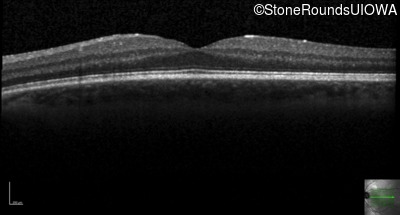

Optical Coherence Tomography - Left - 20/20 -1 sc

Exemplar / OCT Stack

OCT Stack